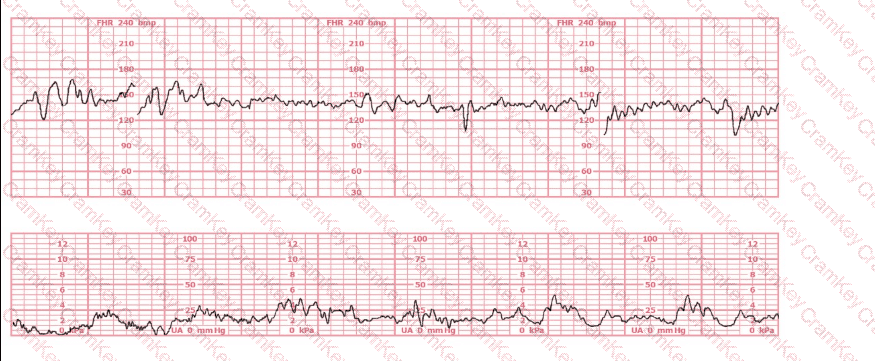

A nulliparous woman at term presents with leaking fluid. Rupture of membranes confirmed. After 6 hours she is completely dilated, +2 station, has been pushing 2 hours with oxytocin at 10 mU/min. The fetal tracing is shown. What is the next step in management?

This is a fetal heart rate tracing of a multiparous woman whose cervix is 7 cm dilated on admission. The most likely cause for this pattern is: